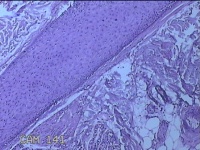

头皮结节

性别

男

年龄

33岁

临床诊断

皮肤赘生物

一般病史

发现头皮结节半个月余,无明显疼痛及不适。

标本名称

大体所见

灰白暗红色带皮肤样结节1x0.8x0.3cm一个,表面糜烂,切开结节呈实性,切面灰白粉红色,质软。

看不清,可能是毛细血管瘤,技术很需提高,不然迟早会。。。